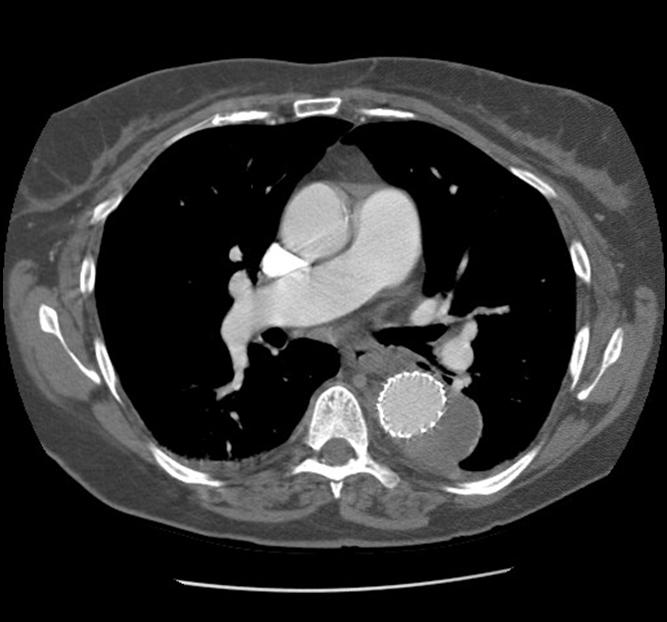

| Figure 2: Three dimensional reconstruction of the chest CT scan |

There were no remarkable findings on physical exam. A chest x-ray revealed a widened mediastinal silhouette, and a high-resolution contrast-enhanced computed tomography (CT) scan was performed using 3mm slices, which demonstrated an isolated 6-cm aneurysm in the mid-portion of the descending thoracic aorta (DTA) (Figure 1). Three dimensional reconstructions were performed from the chest CT scan (Figure 2).